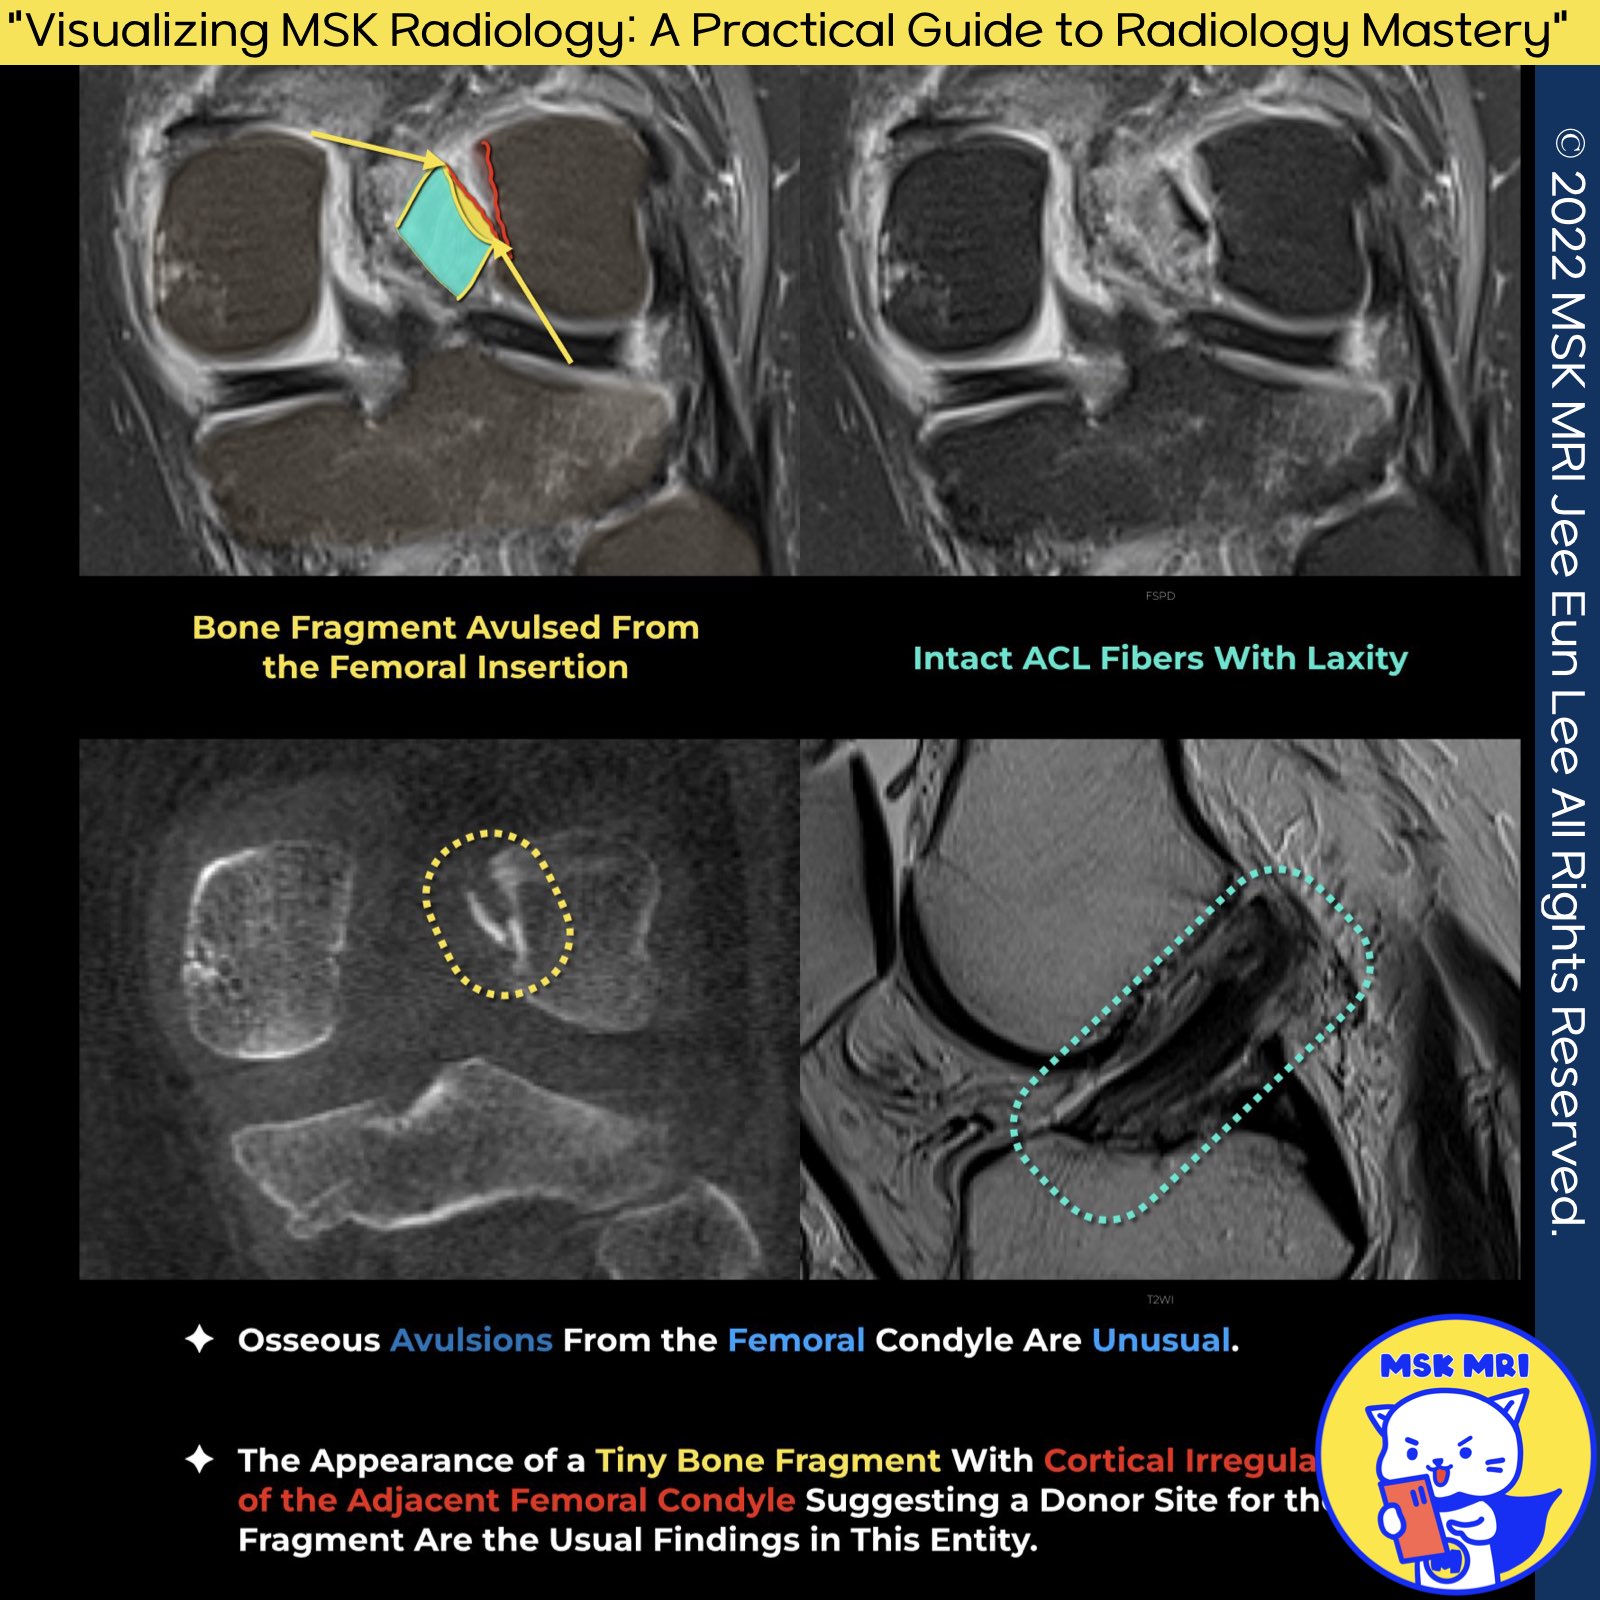

✅ ACL Injuries: Tear and Avulsion Fractures Overview

- Although most ACL tears involve the midsubstance of the ligament, avulsion of its tibial attachment occurs in a minority of cases and is more common in children than adults

- Osseous avulsions from the femoral condyle are unusual.

- It is important to distinguish ligamentous tears from avulsion fractures of the distal ligament insertion, as these may be amenable to primary surgical fixation.